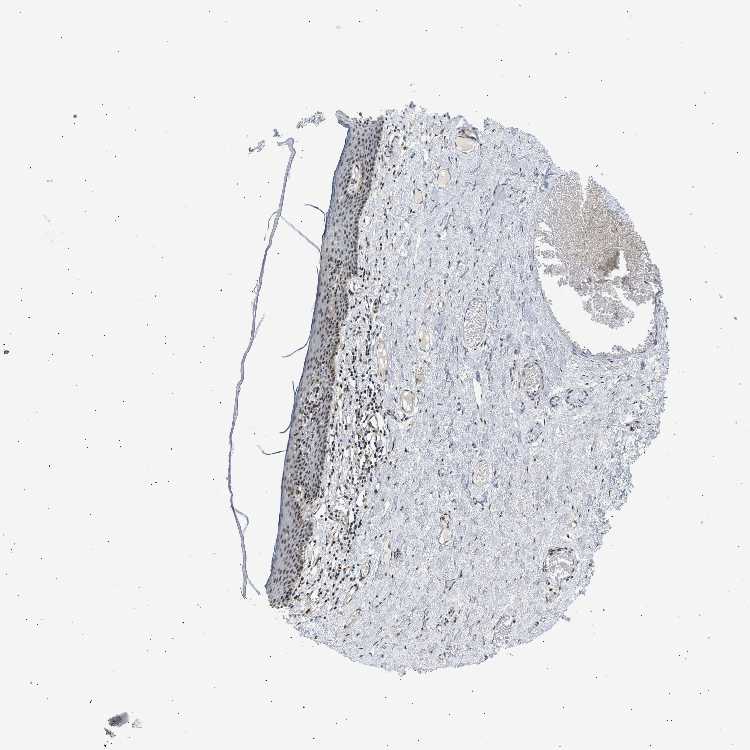

SKIN 2 - Antibody stainingi

Antibody staining in the annotated cell types in the current human tissue is reported as not detected, low, medium, or high, based on conventional immunohistochemistry profiling in selected tissues. This score is based on the combination of the staining intensity and fraction of stained cells.

Each image is clickable and will lead to virtual microscopy that enables deeper exploration of all samples and also displays staining intensity scores, fraction scores and subcellular localization as well as patient and tissue information for each sample.

Antibody HPA019824Antibody CAB015201

Epidermal cells MediumMedium